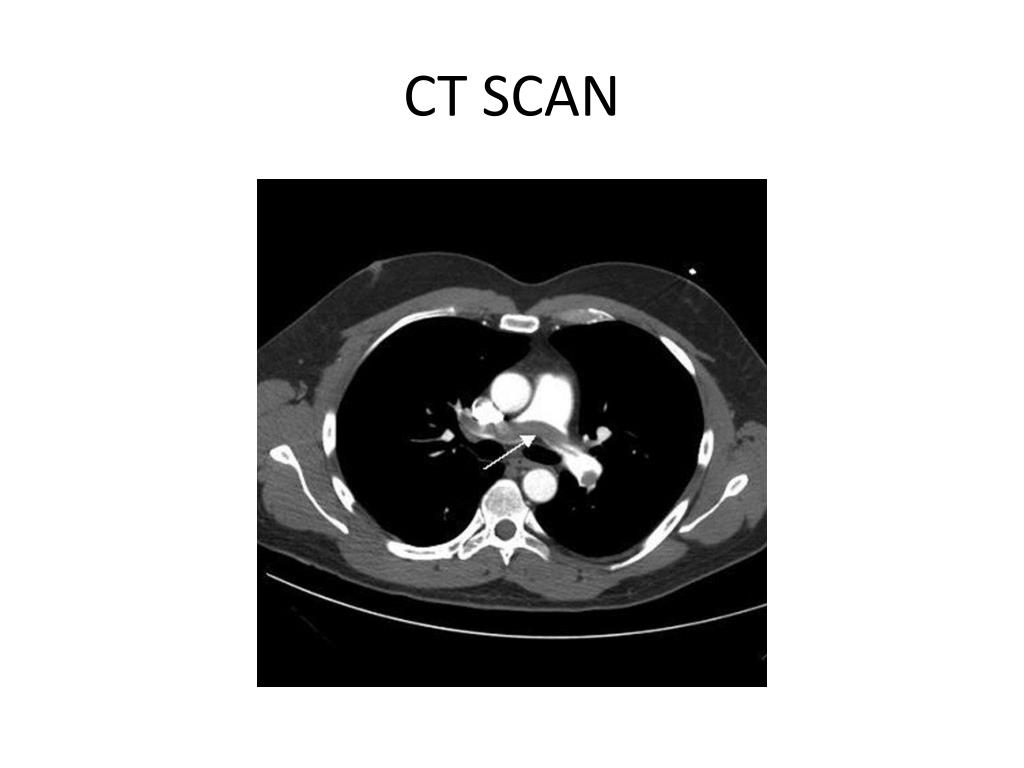

28. NONINVASIVE TESTING • Full PFTs with DLCO help identify COPD Interstitial lung disease • ABG • CT scan Lung pathology Pulmonary embolism • HRCT Interstitial lung disease

29. CT SCAN

30. CT SCAN